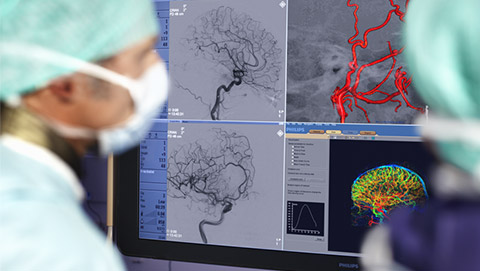

Our Live Image Guidance expands clinical capabilities through intelligent and intuitive integration of multi-modality images at the point of treatment, enabling confident diagnoses and real-time therapy monitoring.

MR/CT Roadmap visualizes lesion boundaries and corresponding vascularization, while helping you to manage X-ray dose and contrast medium. 3D Roadmap provides full 3D view for dynamic guidance of guidewire and catheter navigation through complex vascular lesions.

FlexVision XL visualizes brain vasculature at the capillary level in both 2D and 3D and allows flexible switching of videos sources, screen layout, and image size from tableside.